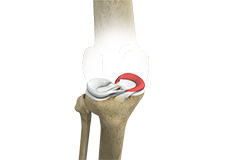

Meniscal Tear

A meniscal tear is a common knee injury in athletes, especially those involved in contact sports. A sudden bend or twist in your knee causes the meniscus to tear. Elderly people are more prone to degenerative meniscal tears as the cartilage wears out and weakens with age.